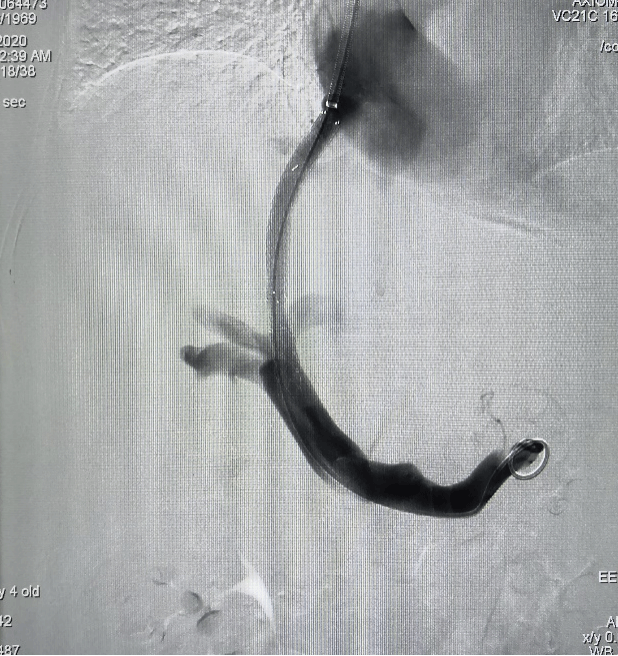

TIPS技术: